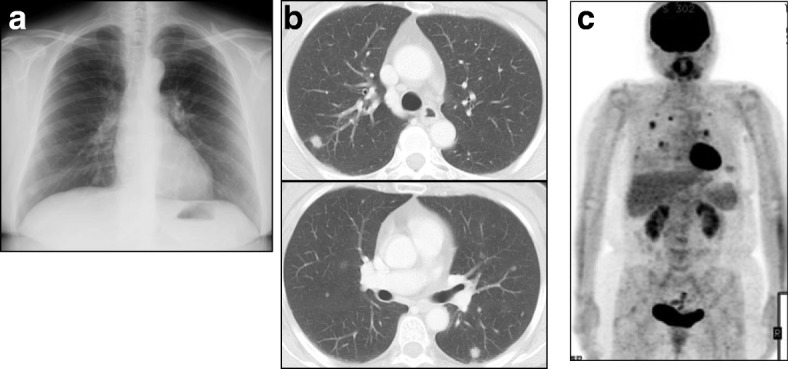

Fig. 1.

a, b Chest X ray (a) and chest computed tomography on admission (b) revealed multiple well-defined nodules in both lungs. c Fluorodeoxyglucose (FDG)-positron emission tomography revealed abnormal FDG uptake in the same lesions with a maximal standardized uptake value (SUV [max]) of 5.6

A 58-year-old Japanese woman presented with chest discomfort and low-grade fever that had persisted for 2 months. She was a dental technician but did not regularly wear a dust mask in the workplace. She previously had a smoking history of 2 pack/year and no medical history. On admission, her body temperature was 37 °C. Physical examination results were almost normal. The laboratory examinations were also normal including blood smear differentials, C-reactive protein, serological tests for autoimmune disorders and malignant and hematological disorders, and serological tests for infectious diseases (Table 1). Chest X ray and computed tomography revealed multiple well-defined nodules in both lungs (Fig. 1a and b) and fluorodeoxyglucose (FDG)-positron emission tomography revealed abnormal FDG uptake in the same lesions with a maximal standardized uptake value (SUV [max]) of 5.6 (Fig. 1c). Then, we performed thoracoscopic partial resection of the lesions in the right upper and middle lobes (Fig. 2a). Histological examination of the specimens revealed foreign body-type giant cells and mild and focal chronic inflammatory changes with the infiltration of lymphocytes and plasma cells together with eosin-positive deposits (Fig. 2b). The deposits were direct fast scarlet (DFS) staining positive and produced an apple-green birefringence under crossed polarized light (Fig. 2d and e). Congo-red staining was also positive (Fig. 2f). Based on these results, we concluded that the substance in the lesion was compatible with amyloid. Although we diagnosed the patient with pulmonary amyloidosis, there was no obvious underlying causes that could typically cause pulmonary amyloidosis, including rheumatoid arthritis, primary Sjögren’s syndrome or multiple myeloma. We also excluded plasma cell neoplasm and multicentric Castleman’s disease because there was no infiltration of atypical plasma cells nor formation of multicentric lymphoid follicles in the lesions. Consequently, we focused on her occupational history and performed electron probe X-ray microanalysis (EPMA) of the specimens to evaluate the cause of pulmonary amyloidosis. EPMA of the specimens revealed the deposition of silica throughout the granulomatous lesions as well as among giant cells (Fig. 2g and h). From these results, we finally diagnosed the patient with multiple lung granulomas with amyloid deposition caused by chronic silica exposure. Afterward, her symptoms improved and the disease has not progressed for 2 years since proper measures against additional occupational exposure were implemented.